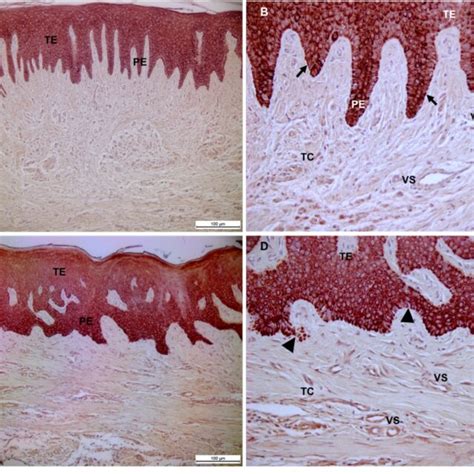

Desde el punto de vista histológico y ultramicroscópico, la encía se compone de dos tejidos principales: un epitelio gingival estratificado y un tejido conectivo subyacente (también llamado corion o lámina propia).

Epitelio Gingival

El epitelio de la encía presenta regiones con distintas características según su ubicación. En la superficie externa, expuesta a la cavidad bucal, el epitelio gingival está queratinizado (orto o paraqueratinizado) para resistir las fuerzas de la masticación - similar al epitelio de la piel, aunque más delgado. Hacia el interior, revestiendo la pared del surco gingival (el pequeño espacio entre el diente y la encía libre), el epitelio se torna no queratinizado y se denomina epitelio sulcular. Este epitelio sulcular tapiza la cara interna de la encía marginal y forma un fondo de saco de aproximadamente 0,5 mm de profundidad en encías sanas.

Apicalmente, en el fondo mismo del surco, el epitelio sulcular se continúa con el epitelio de unión (o epitelio de inserción dentogingival). El epitelio de unión es una capa especializada de células epiteliales no queratinizadas que adheren la encía al diente: sus células están unidas al esmalte del diente (en la zona del cuello, cerca de la unión amelocementaria) mediante hemidesmosomas, creando un sello epitelial alrededor del diente. Este epitelio de unión tiene unos 0,5-1 mm de altura vertical y, en condiciones normales, se ubica a nivel o ligeramente por debajo de la unión cemento-esmalte, constituyendo el mecanismo biológico de inserción más coronal del diente.

Tejido Conectivo Gingival (Lámina Propia)

Bajo el epitelio, el tejido conectivo gingival (lámina propia) le da soporte y elasticidad a la encía. Está formado por una densa red de fibras de colágeno tipo I (predominante) dispuestas en distintas direcciones, células conectivas y una matriz extracelular intersticial de proteoglicanos y glicoproteínas. El colágeno representa cerca del 60% del volumen del tejido conectivo gingival, la sustancia fundamental un ~35% y las células apenas un 5%.

Entre las fibras colágenas, pueden distinguirse haces que van del diente a la encía (fibras dentogingivales, que se insertan en el cemento radicular del diente), del diente al hueso (fibras dentoalveolares o dentoperiósticas, hacia el periostio del hueso) y fibras circulares que rodean circunferencialmente al diente dentro de la encía marginal. Este entramado fibroso ancla firmemente la encía al diente y al hueso, manteniendo su posición y resistencia. Las células principales de la lámina propia son los fibroblastos gingivales, responsables de sintetizar colágeno y componentes de la matriz. También se hallan numerosas células inmunitarias (leucocitos, macrófagos, plasmocitos, mastocitos) que residen en la encía o migran hacia ella ante la presencia de placa bacteriana, conformando un sistema inmunitario local activo.